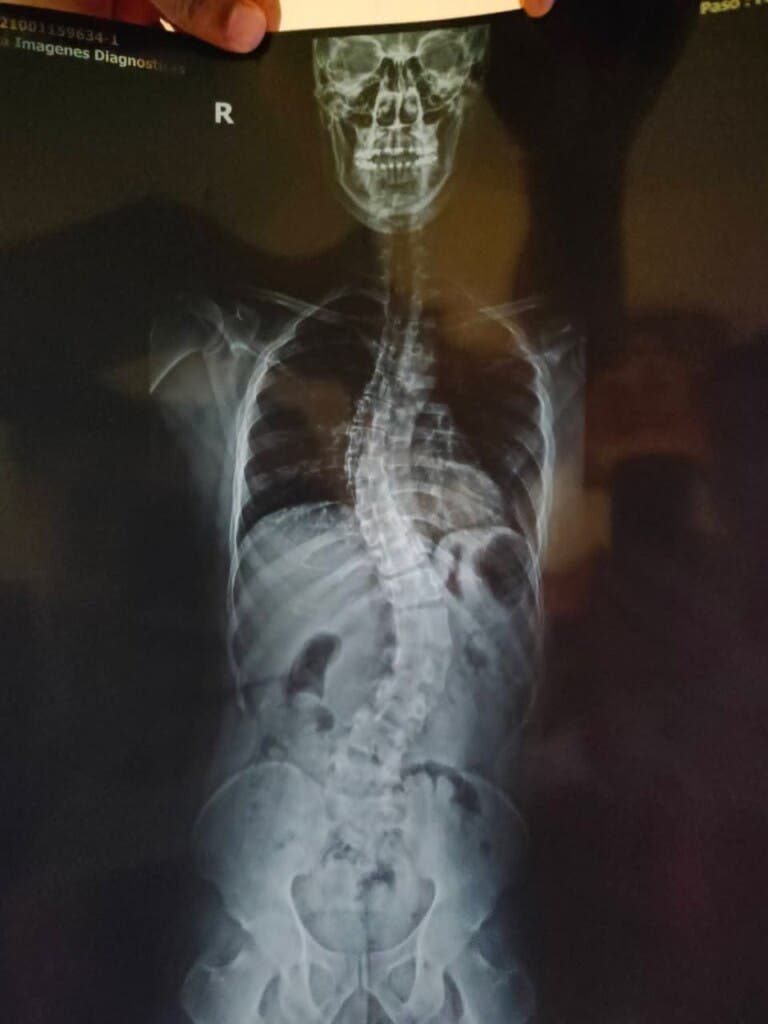

Posteriormente, los especialistas determinaron que presentaba tornillos mal colocados en la columna vertebral, situación que provocó infecciones recurrentes y un deterioro continuo de su estado de salud. Actualmente padece osteomielitis vertebral, una grave infección ósea localizada en la columna lumbar (L4-L5), de acuerdo con estudios médicos recientes.